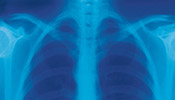

圖1關於吸入性損傷的分類標準尚不統一。有的按病情嚴重程度分為輕、中、重三類或輕、重兩類;有的按損傷部位分為上、下氣道及肺實質損傷。目前國內多數採用三度分類法(圖1)。

以往認為X線對呼入性損傷無診斷意義。但王天乙等(1980)和楊智義等(1982)通過動物實驗和臨床觀察認為,取右前斜位X線攝片,傷後2~6小時出現明顯的氣管狹窄,氣管內顯示斑點狀陰影響,透光度減退,黏膜不規整,早期顯示氣管狹窄的特徵,可作為吸應的X線改變。肺水腫時顯示彌散的、玻片狀陰影、葉間影象、肺門擴大、線形或新月形影象;肺部感染時可見中心性浸潤影象或瀰漫而稠密的浸潤影象;有時可看到由於代償性肺氣腫所顯示的氣球樣透明度增強,以及由於肺泡破裂或氣腫樣大泡破裂所致的氣胸影象。

③肺部體徵及X線拍片:當病人出現呼吸衰竭時,早期胸片顯示透明度低、肺紋理增多、增粗,與呼吸困難體徵不相符。當肺部出現乾、濕羅音,胸片出現雲片狀陰影時,多已屬晚期。